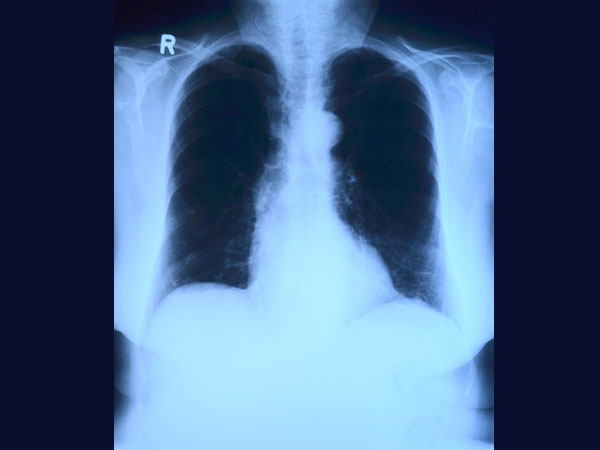

ನವಂಬರ್ 18ರಂದು ಮೊಹಮ್ಮದ್ ಮಕ್ಸೂದ್ ತೀವ್ರ ಹೊಟ್ಟೆ ನೋವೆಂದು ಆಸ್ಪತ್ರೆಗೆ ದಾಖಲಾಗಿದ್ದ. ಎಕ್ಸರೇ ತೆಗೆದ ಬಳಿಕ ಆತನ ಹೊಟ್ಟೆ ನೋವಿಗೆ ಕಾರಣ ತಿಳಿದುಬಂದಿದೆ. ಆದರೆ ಶಸ್ತ್ರಚಿಕಿತ್ಸೆ ವೇಳೆ ನಾಣ್ಯ ಮತ್ತು ಇತರ ಲೋಹದ ವಸ್ತುಗಳನ್ನು ತೆಗೆಯುವಾಗ ವೈದ್ಯರಿಗೆ ಅಚ್ಚರಿಯಾಗಿದೆ.

ಸುಮಾರು ಆರು ಮಂದಿ ತಜ್ಞ ವೈದ್ಯರ ತಂಡವು ಮೊಹಮ್ಮದ್ ಮಕ್ಸೂದ್ ಹೊಟ್ಟೆಯೊಳಗೆ ಇದ್ದ ಲೋಹಗಳನ್ನು ತೆಗೆಯಲು ಶಸ್ತ್ರಚಿಕಿತ್ಸೆಯಲ್ಲಿ ಭಾಗಿಯಾಯಿತು. ಸುಮಾರು 5 ಕೆಜಿ ಭಾರದ ಲೋಹಗಳನ್ನು ವೈದ್ಯರ ತಂಡವು ಹೊಟ್ಟೆಯಿಂದ ಹೊರತೆಗೆದಿದೆ. ಮಕ್ಸೂದ್ ಹೊಟ್ಟೆಯಿಂದ ನಾಲ್ಕು ದೊಡ್ಡ ಸೂಜಿ, ಒಂದು ಸರ, 263 ನಾಣ್ಯ, 10-12 ಬ್ಲೇಡ್ ಗಳು ಮತ್ತು ಕೆಲವು ತುಂಡು ಗಾಜುಗಳಿದ್ದವು. ಇದು ತುಂಬಾ ಆಘಾತಕಾರಿ ಪ್ರಕರಣವಾಗಿದೆ ಮತ್ತು ವೃತ್ತಿಯಲ್ಲಿ ಇದೇ ಮೊದಲ ಸಲ ಇಂತಹ ಪ್ರಕರಣ ನೋಡುತ್ತಿದ್ದೇವೆ ಎಂದು ವೈದ್ಯರು ತಿಳಿಸಿದ್ದಾರೆ. ಶಸ್ತ್ರಚಿಕಿತ್ಸೆ ತುಂಬಾ ಬೇಗನೆ ಮಾಡಬೇಕಿತ್ತು. ಯಾಕೆಂದರೆ ಕೆಲವು ಲೋಹಗಳು ಹೊಟ್ಟೆಯಲ್ಲಿ ಚುಚ್ಚಿಕೊಂಡು ರಕ್ತಸ್ರಾವವಾಗುತ್ತಿತ್ತು. ಇದರಿಂದ ಹಿಮೋಗ್ಲೋಬಿನ್ ಕಡಿಮೆಯಾಗುತ್ತಿತ್ತು ಎಂದು ವೈದ್ಯರು ತಿಳಿಸಿದ್ದಾರೆ.